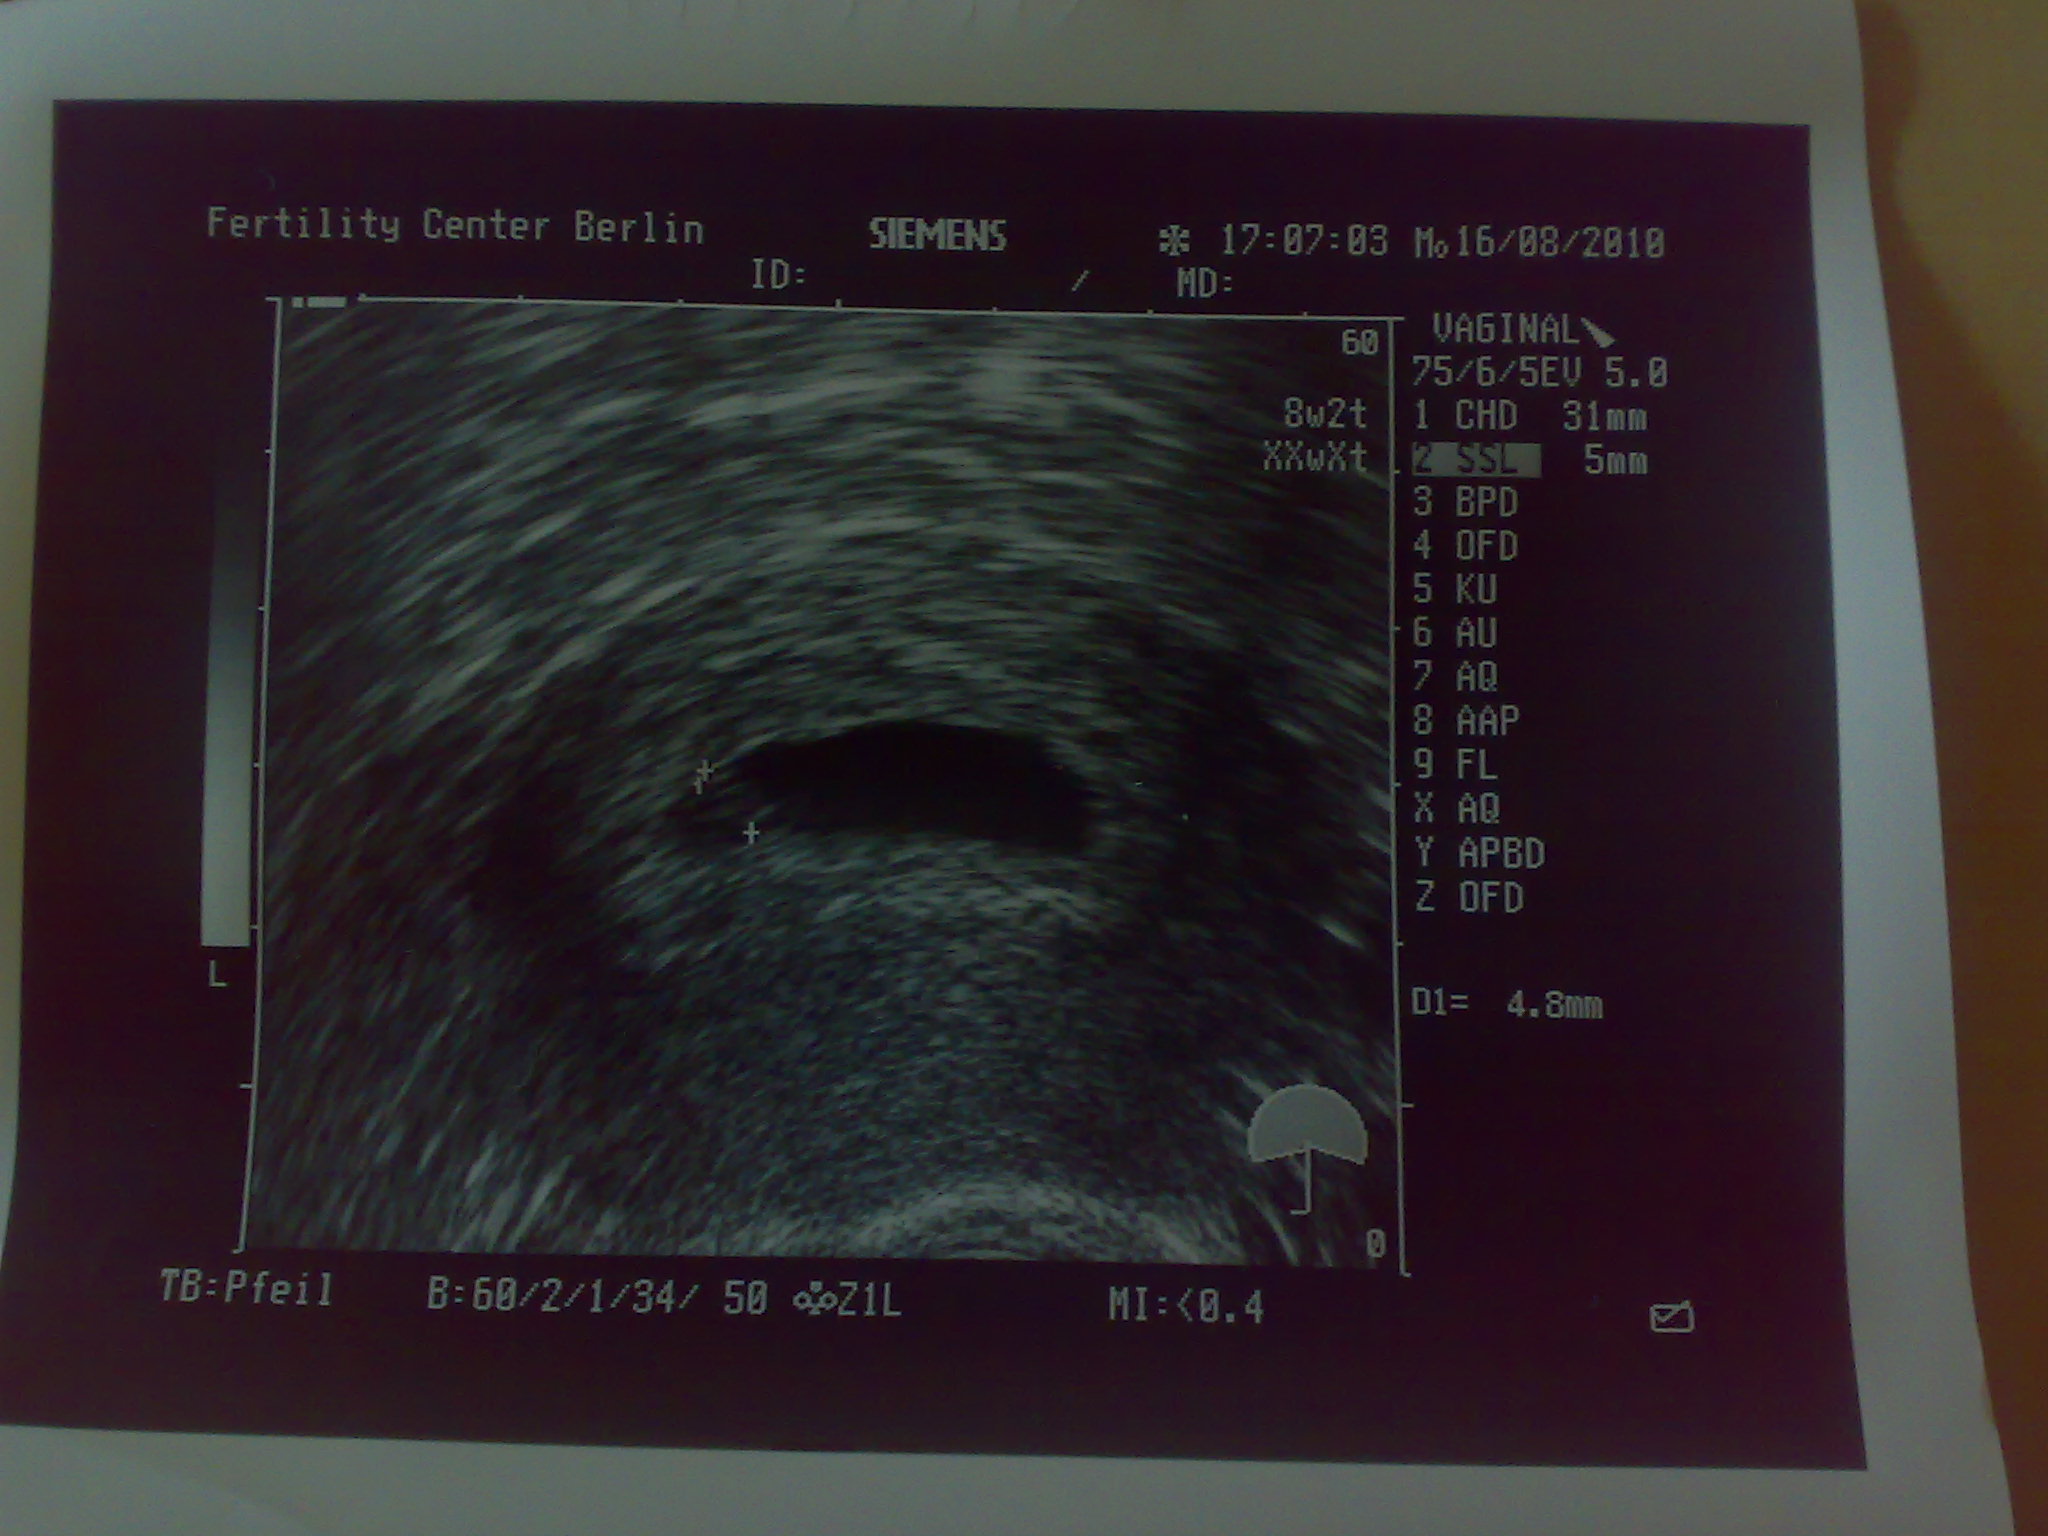

@ me: Mein Termin beim KiWu-Doc:

Zunächst hab ich jetzt erst mal die Info, dass sie einen Fall wie meinen noch nie in der Praxis hatten.

Aber immerhin hat man mich nun nicht als komplett hoffnungslosen Fall aus der Behandlung entlassen.

Von den 6 EZ hatte sich jetzt doch eine befruchten lassen, ABER diese hatte auch wieder einen irregulären Chromosomensatz. D. h. ich hab die auch nicht transferiert bekommen.

Aufgrund dieses Ergebnisses ist man sich nun relativ sicher, dass unsere Sterilität eine genetische Ursache hat.

Wahrscheinlich liegt wohl ein Defekt in der Meiose II vor. Bei wem von uns ist unklar.

Der Plan des KiWu-Docs sieht nun vor, dass wir Ende Oktober nochmals einen IVF/ICSI Zyklus machen werden.

Dabei soll mit dem Antagonisten Protokoll mit mehr Einheiten Puregon gezielt eine Überstimu mit 16 EZ+ durchgeführt werden. Die EZ die er dabei zu erhalten hofft sollen zur Hälfte mit ICSI und zur anderen Hälfte mit IVF-Behandlung (hoffentlich) befruchtet werden. Die Hoffnung ist dabei, dass wir reguläre Embryonen erhalten.